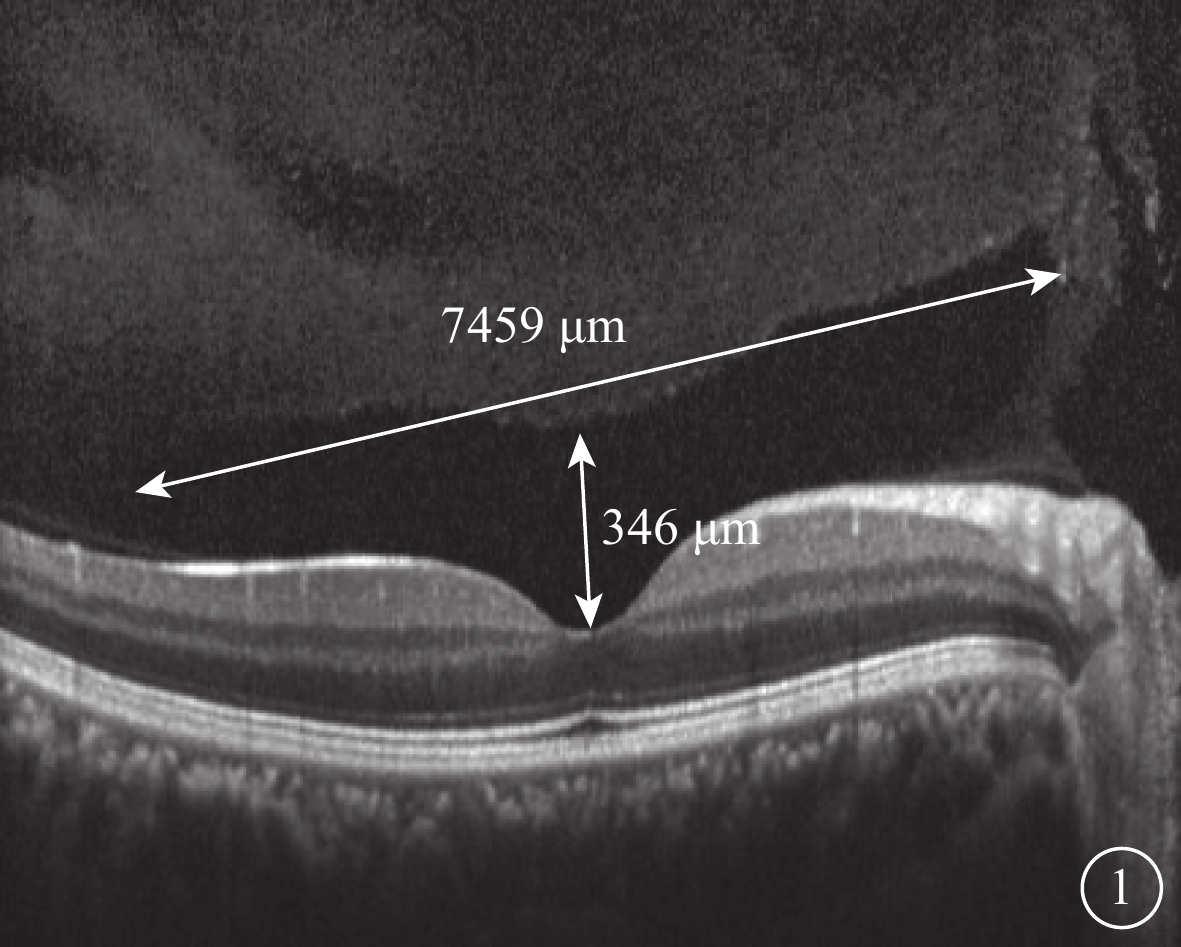

SS-OCT檢查結果顯示,所有受檢眼均在同一掃描層面觀察到PPVP與Martegiani區(圖6),其中PPVP與Martegiani區存在連接通道54只眼(77.0%)。其形態特點與SD-OCT檢查所見相似,但PPVP成像更清晰,與Martegiani區的連接通道更清楚(圖6)。PPVP前存在黃斑上囊7只眼。PPVP伴PVD 4只眼,其中玻璃體后皮質破裂后界不完整(圖7)2只眼。同時行SD-OCT及SS-OCT檢查的24只眼中,SD-OCT、SS-OCT檢查發現PPVP與Martegiani區連接通道分別為18、21只眼;SD-OCT檢查未發現黃斑上囊2只眼,但SS-OCT檢查發現存在。

圖7

受檢眼SS-OCT像。可見明顯PVD(白箭)伴PPVP(黃色星);PPVP后界破裂,與PVD產生出現連接通道

圖7

受檢眼SS-OCT像。可見明顯PVD(白箭)伴PPVP(黃色星);PPVP后界破裂,與PVD產生出現連接通道

SS-OCT檢查結果顯示,所有受檢眼均在同一掃描層面觀察到PPVP與Martegiani區(圖6),其中PPVP與Martegiani區存在連接通道54只眼(77.0%)。其形態特點與SD-OCT檢查所見相似,但PPVP成像更清晰,與Martegiani區的連接通道更清楚(圖6)。PPVP前存在黃斑上囊7只眼。PPVP伴PVD 4只眼,其中玻璃體后皮質破裂后界不完整(圖7)2只眼。同時行SD-OCT及SS-OCT檢查的24只眼中,SD-OCT、SS-OCT檢查發現PPVP與Martegiani區連接通道分別為18、21只眼;SD-OCT檢查未發現黃斑上囊2只眼,但SS-OCT檢查發現存在。

圖7

受檢眼SS-OCT像。可見明顯PVD(白箭)伴PPVP(黃色星);PPVP后界破裂,與PVD產生出現連接通道

圖7

受檢眼SS-OCT像。可見明顯PVD(白箭)伴PPVP(黃色星);PPVP后界破裂,與PVD產生出現連接通道